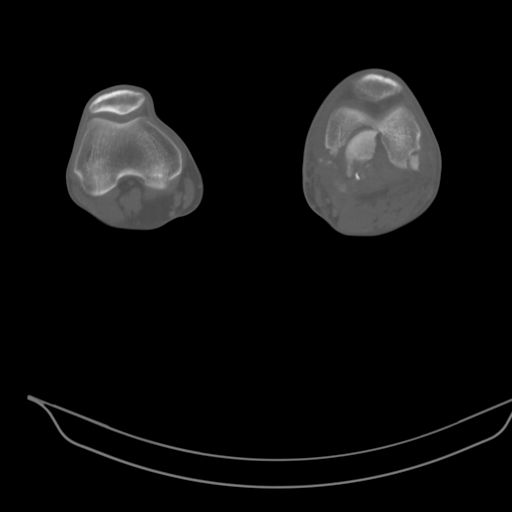

CT shows major bony fragments which are markedly rotated .With this amount of bony damage,you probably should attempt to get reasonably loooking knee with ORIF and thn if he needs a TKR due to pain a few years from now, then tleast you have something looking like a knee that you can replace rather than having to use revision knee for a primary TKR now. 4 weeks is not too long .what is the condition of soft tissues?

При внутрисуcтавных переломах трехмерные (3D) изображения, кроме красивого снимка, не дают полную информацию о состоянии отломков, самыми информативными являются корональные срезы на КТ и обычная длинная ренгенограмма конечности для сравнения оси конечности.

Фронтальные внутрисуставные переломы мыщельков бедра, так называемые Hoffa fracture, не частые, но встречающиеся переломы, в основном они связаны с травмой высокой энергией.

В зависимости от смещения рекомендуется сопоставление костных фрагментов с последующей жесткой фиксацией.

В вашем случае доступ будет медиальный, сопоставить развернутый медиальный мыщелок и фиксацию надо произвести в передне-заднем

направлении шурупами 4.5 мм в диаметре, углубив головку шурупов под хрящ, а поперечную фиксацию - межмыщелковыми шурупами. Желательно применить шурупы 6.3 мм в диаметре. Дополнительная Buttress technique пластина предотвратит перелом от скольжения.